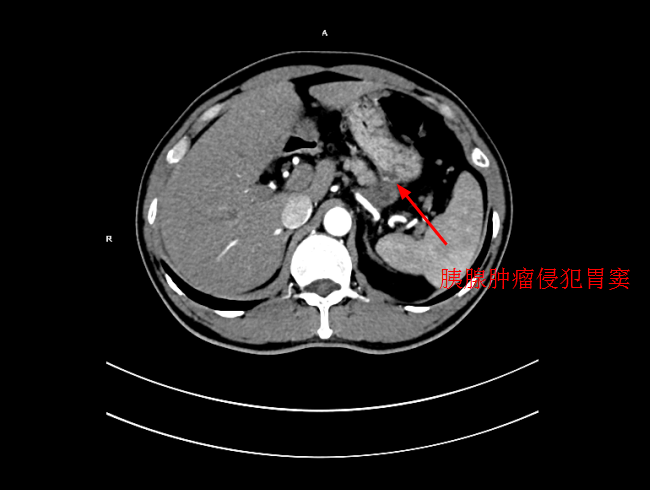

患者陳某,男,49歲,2個月前出現中上腹隐痛不适,伴有腰背部疼痛,在當地醫院就診,考慮爲胃窦炎、胃窦黃斑瘤,治療後症狀未見好轉,遂來我院就診。經過檢查後,确診爲局部晚期胰腺癌,大小爲5*3cm,癌細胞已侵犯胃窦。考慮到傳統化療方式,藥物經身體多重代謝後,到達胰腺的濃度低,達不到很好殺滅腫瘤組織的效果,且對正常組織具有一定的毒副作用。爲此李旭丹主任決定給予采用DSA下介入灌注化療,得到患者及其家屬的支持。